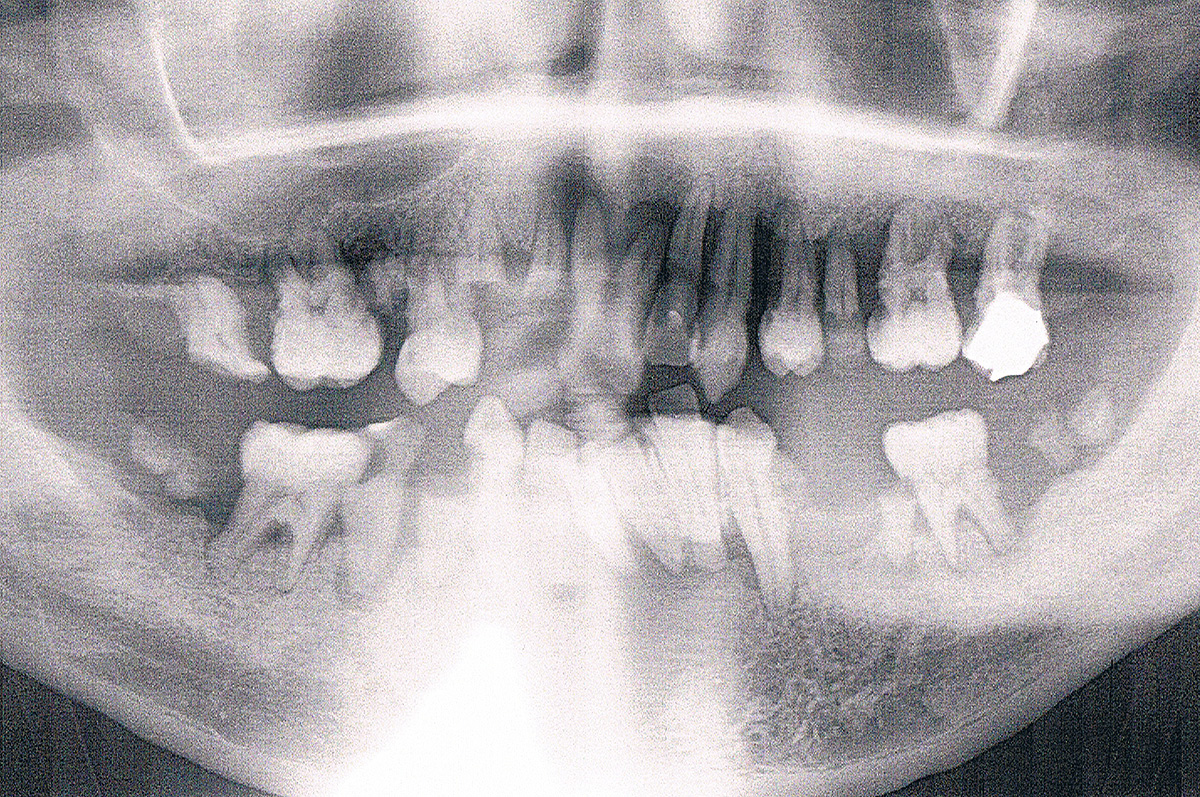

レントゲンやCTで口腔内の撮影を行い、目に見えない隠れた病気を発見します。 歯形を取り、上下のかみ合わせのバランス、歯並びを見ます。 その診断結果についてはカウンセリングの時にご説明いたします。